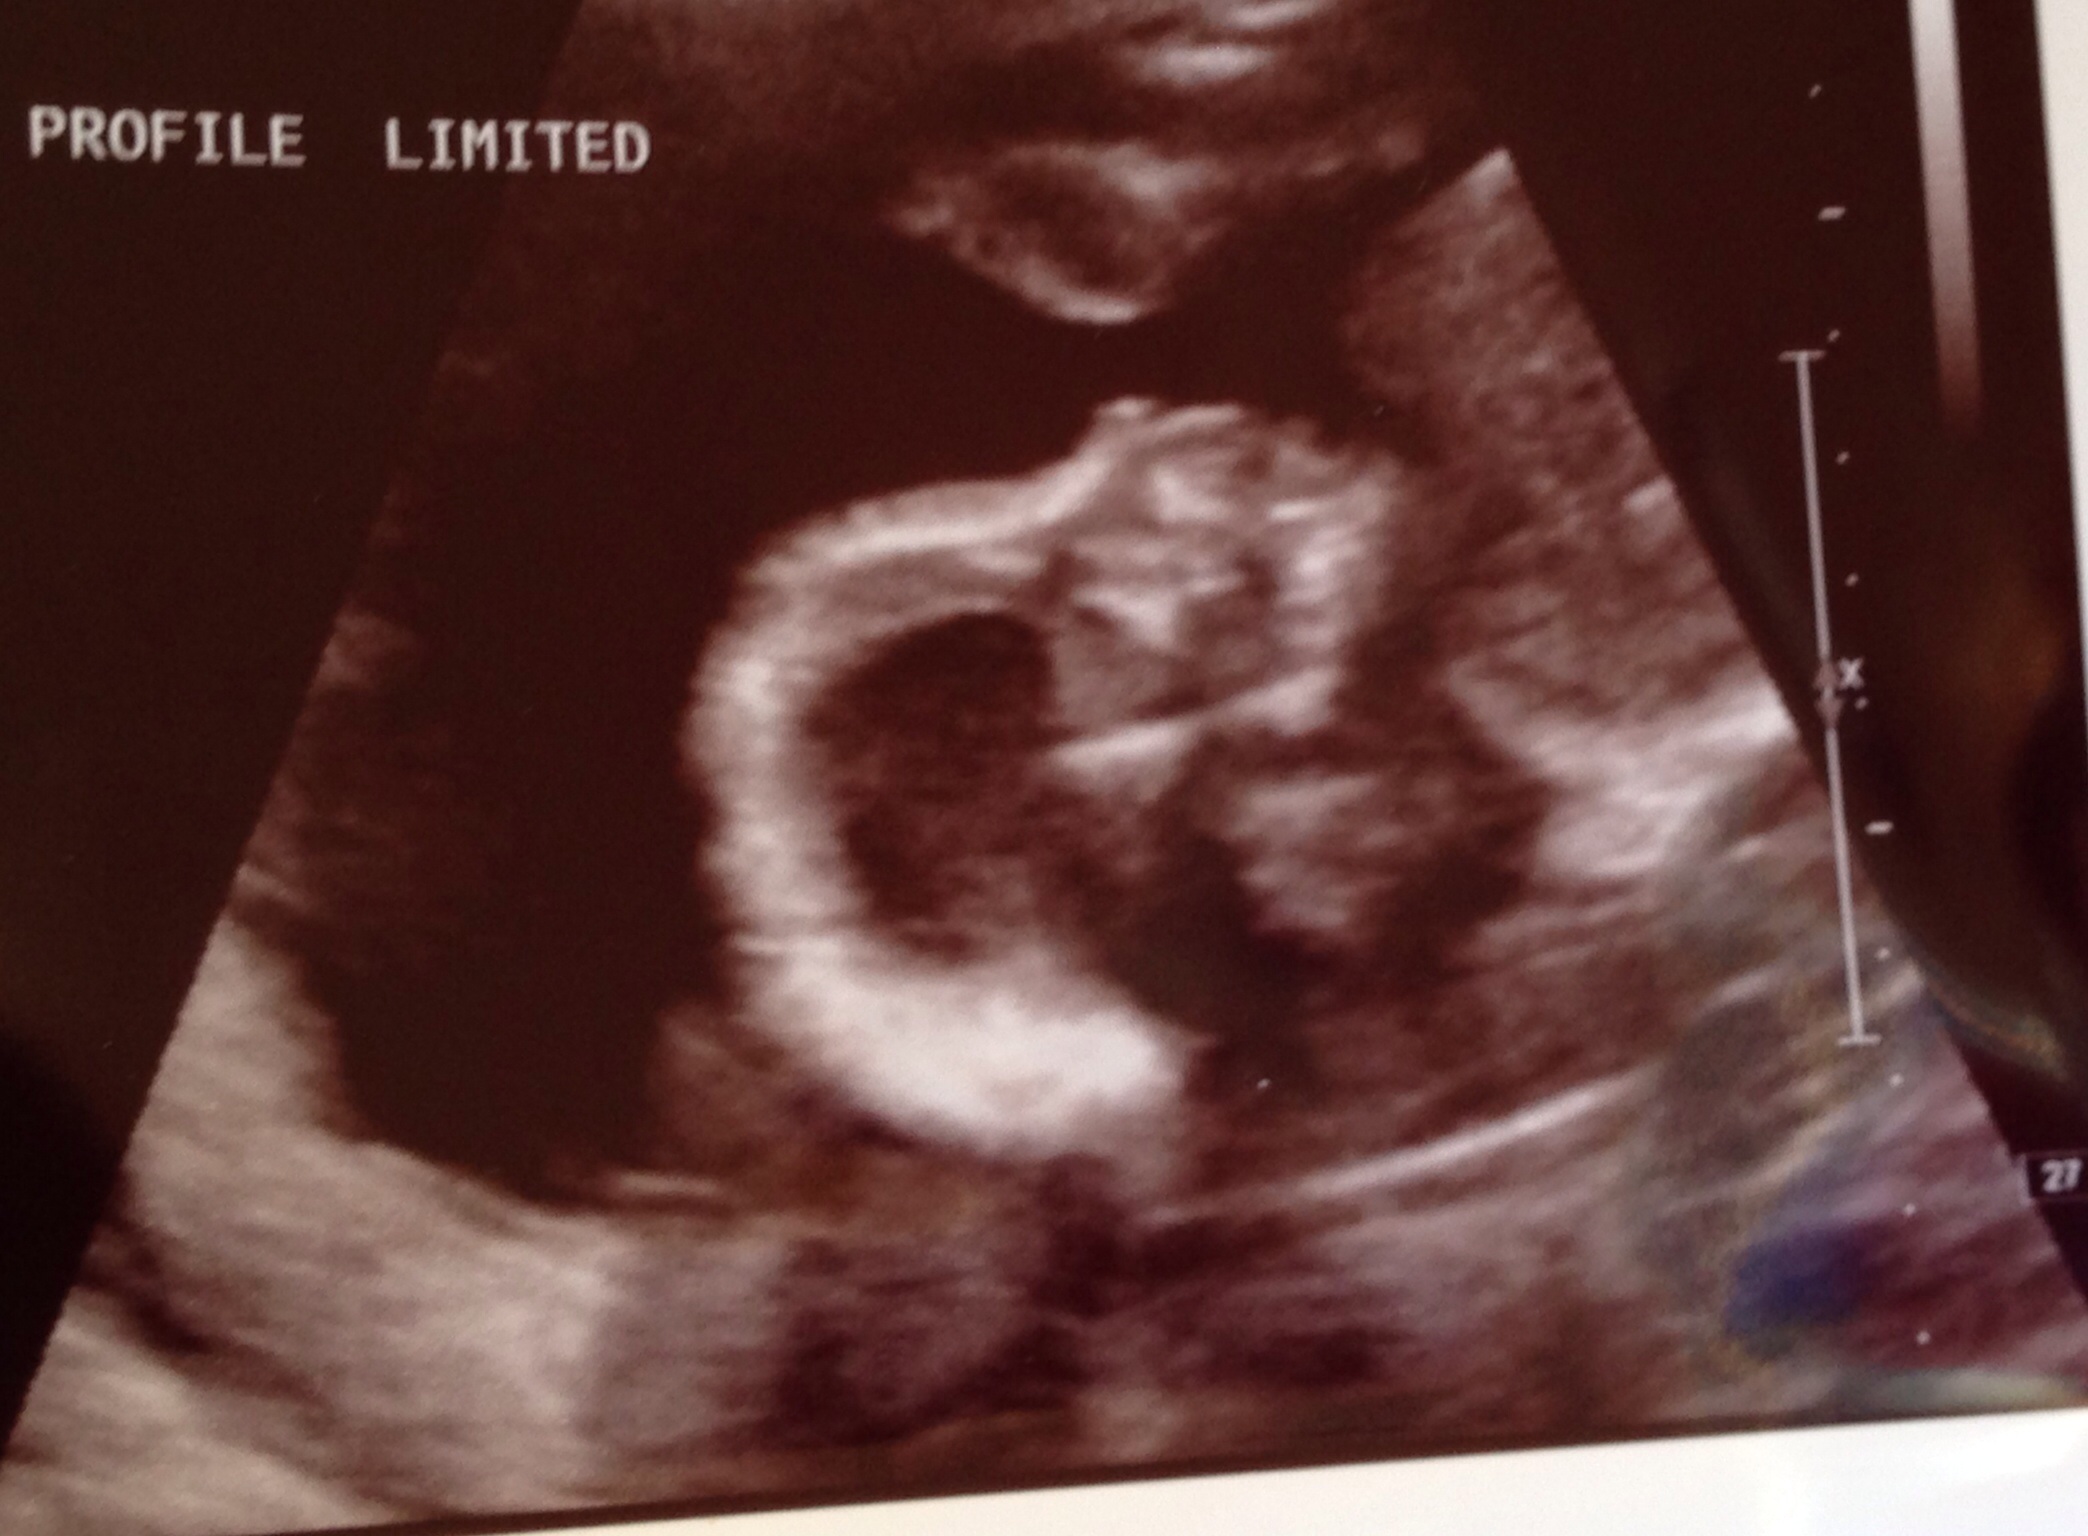

• So I got my A/S done last Tuesday. I was super excited everything came out well, since that's what this scan us and l about (and we got to find out the sex).

My problem is, though, that we have a couple great pics from our first two ultrasounds (at around 8 weeks and 12 weeks) and I really wanted a good second tri ultrasound pic. Well, all the ones we got are really blurry, and of feet (but not even a good foot photo). I got two 'creepy' baby faces. (This is what my mom called them ... and I fully agree that they look like a skull staring at you).

So, all this tl, dr: Where can I go to find a place (Even to pay) to get a couple good Ultrasound photos? How did you find a good/reputable place to use?

• So I got my A/S done last Tuesday. I wjas super excited everything came out well, since that's what this scan us and l about (and we got to find out the sex).

i love our skeleton faced baby!! Haha. But we just went with google reviews and word of mouth.